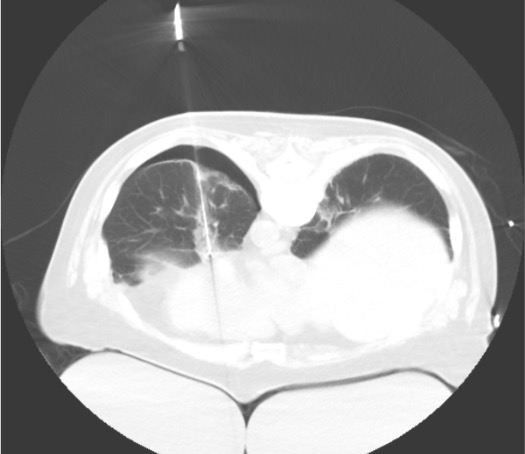

- CT guidance required — interventional CT suite; CT fluoroscopy or step-and-shoot

Positioning & CT Planning Scan

Probe Placement

Post-Ablation CT

- Ground-glass opacity (GGO) halo — surrounds treated lesion; represents reactive inflammation and hemorrhage; a 1-cm GGO halo around the entire lesion = adequate margin; this is the primary adequacy endpoint